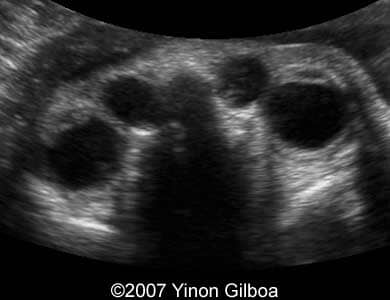

These are some ultrasound images obtained at 30th week of pregnancy. Previous ultrasonography scans at 15th and 24th week were normal. Our investigation revealed bilateral dacryocystocele of the fetus. No other anomalies were found.

Image 1: Transverse scan at the level of the fetal eyes showing bilateral dacryocystocele.